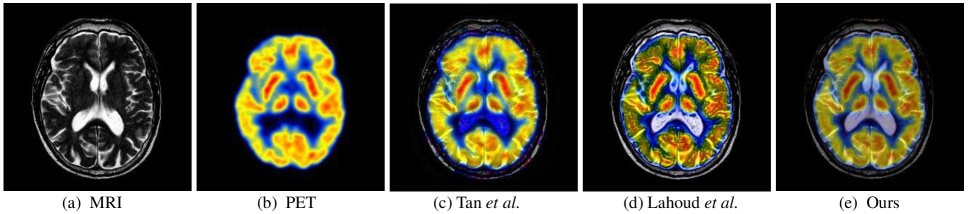

Fig. 1: The fusion results for MRI and SPECT images using different methods. Tan et al. [4] weakens the features of SPECT. Lahoud et al. [13] over-enhances textures of MRI. Our method generates image (e) with smoother transitions between modalities while retaining appropriate details.

These methods can be divided into multi-scale transform [3, 4], sparse representation [5], subspace [6], hybrid models [7], saliency-based [8], and other methods [1]. Although these conventional methods could achieve satisfactory results in many cases, they tend to weaken the essential characteristics of source images [see Fig. 1(c)].

Benefiting from its strong ability of feature extraction and representation, deep learning has many applications in multimodal image fusion. Prabhakar et al. [9] proposed a convolution-based network termed as Deepfuse for multi-exposure image fusion (MEF). Based on Deepfuse, Li et al. [10] proposed the visible and infrared image fusion network DenseFuse, by replacing the feature extraction layer with dense blocks and redesigning the fusion strategy. Ma et al. [11] proposed an infrared and visible image fusion framework based on a generative adversarial network (GAN). Xu et al. [12] used a weight block to measure the importance of information from different source images. Lahoud et al. [13] proposed to extract feature maps of multimodal medical images using a pre-trained network and designed a weight fusion strategy with these feature maps. Recently, several studies presented to combine fusion with high-level vision tasks. Tang et al. [14] proposed SeAFusion, which bridged the gap between image fusion and semantic features. While these methods are valid for most fusion scenes, they emphasize the differences between different modal images without exploring their correlations. As shown in Fig. 1(d), the approach of Lahoud et al. [13] enhances the features of each of the two modals, but also introduces too many trivial textures.

From Table 2, our method achieves the best performance on PSNR and QcvsubscriptQ𝑐𝑣\mathrm{Q}_{cv}, both for Medical and VI-IR. The excellent performance on QcvsubscriptQ𝑐𝑣\mathrm{Q}_{cv} illustrates that the images produced by our method are more in line with human visual perception. From Fig. 4, the method of Tan et al. leads to a low weight of MRI image, while our approach preserves these elements well. The image generated by Tan et al. introduces an excessive amount of details, while our method reconciles the details of the two modalities. As exhibited in Fig. 5, DenseFuse and FusionGAN fail to preserve the visible parts of the board. U2Fusion has a lower ability to highlight salient targets from infrared images. In general, the images achieved by our method have the best visual performance.